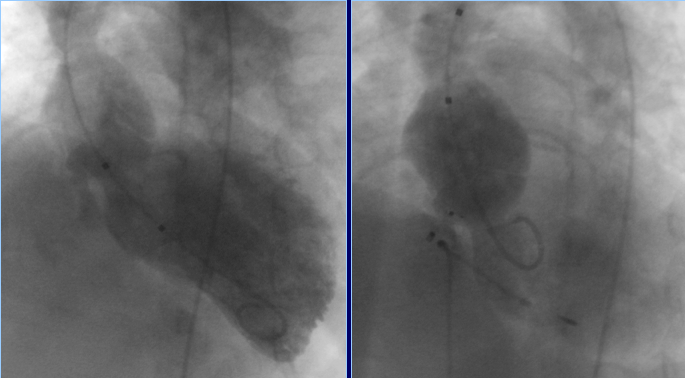

Спустя 3 месяца одномоментное биллатеральное стентирование устьевых стенозов легочных артерий

Операция: Одномоментное стентирование устьевых стенозов обеих легочных артерий